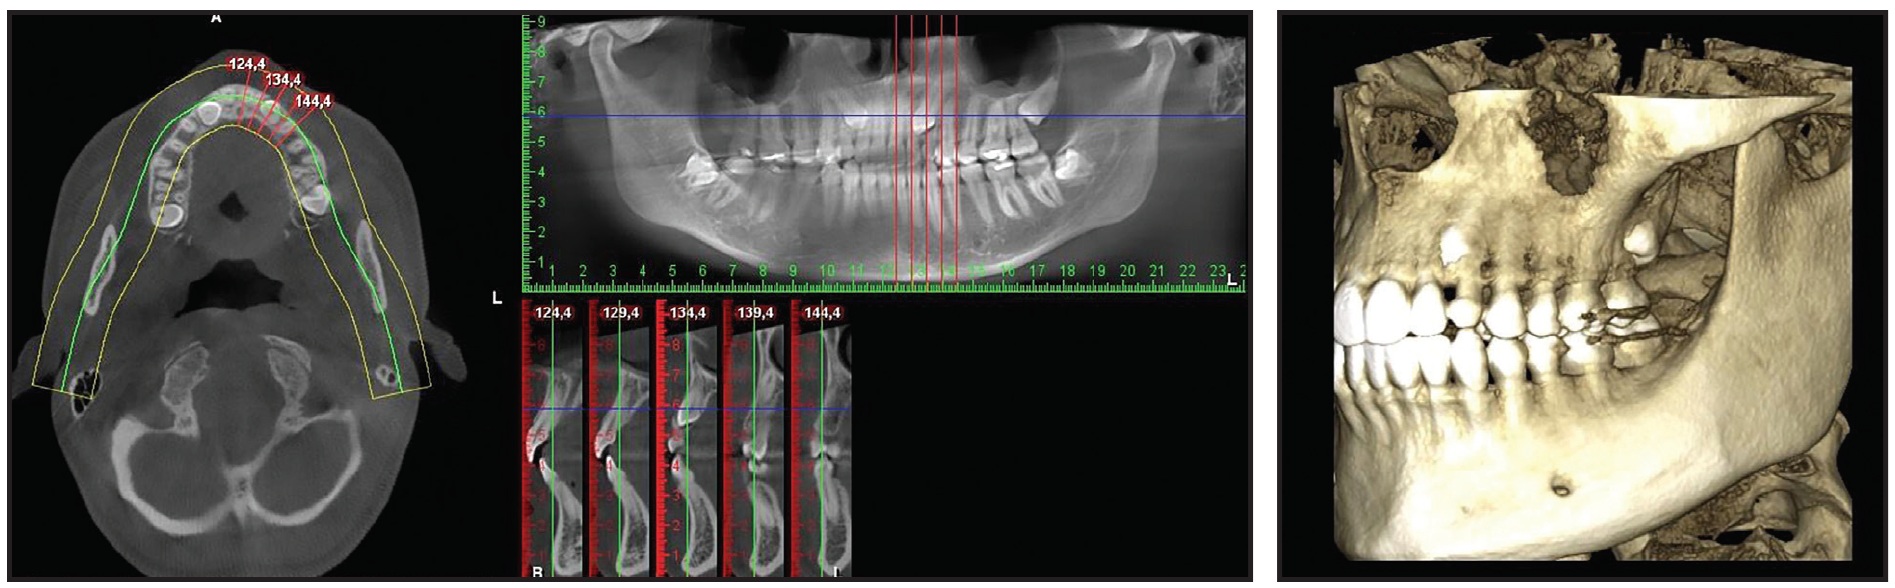

The panoramic radiograph showed that both upper canines were impacted and slightly overlapping the roots of the lateral incisors. Cone-beam computed tomography (CBCT) evaluation revealed a palatal position of the left canine and a mid-crestal position of the right canine (Fig. 1B).

Fig. 1 (cont.) Case 1. 22-year-old female patient with bilaterally impacted upper canines before treatment.

The panoramic radiograph revealed an impacted upper right canine overlapping the roots of the lateral and central incisors.

A 29-year-old male presented with the chief complaint of a gap between his upper front teeth (Fig. 11). The soft-tissue profile was straight, with mildly retrusive upper and lower lips, 50% incisor display in smiling, and a flat smile arc. The mandibular midline was deviated 3mm to the left of the facial midline, and there was a 2mm diastema between the upper central incisors; the overbite was 1-2mm. Class III molar and canine relationships were present on the right side, and Class I relationships on the left. The maxillary arch was constricted compared to the mandibular arch, with a crossbite from the left canine to the left second molar. The lower left deciduous canine was retained, and mild crowding was noted in the mandibular arch. The upper right lateral incisor was in an edge-to-edge relationship with the lower right canine, while the upper left incisor was in an anterior crossbite. Bolton analysis indicated a 2.07mm mandibular excess due to the narrow mesiodistal width of the upper lateral incisors (6mm each).

Fig. 11 Case 3. 29-year-old male patient with horizontally impacted upper left canine, diastema between upper central incisors, Class III molar and canine relationships on right side, left buccal crossbite, and Bolton discrepancy before treatment.

The panoramic radiograph revealed that the upper left canine was horizontally impacted, overlapping the root of the upper left lateral incisor. Cephalometric analysis indicated a Class III skeletal relationship (ANB = –1°, Wits appraisal = –3mm) with a normal vertical dimension (MPA = 34°). Both the upper and lower incisors were retroclined.